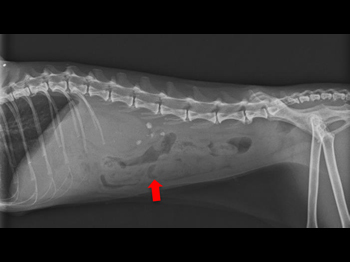

他院より紹介されたケース、この猫ちゃんは左右尿管に 結石(矢印)が詰まっていました。

尿管結石が原因で腎臓は水腎症になっていました。